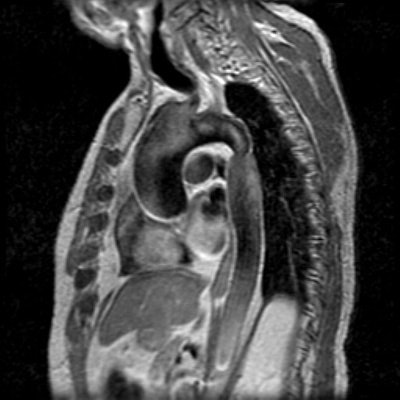

The patient below was noted to have asymmetric pulses between the upper and lower extremities. The off-axis sagittal T1 weighted image demonstrates a focal narrowing of the descending thoracic aorta just beyond the ligamentum arteriosum. (Click on images to enlarge)